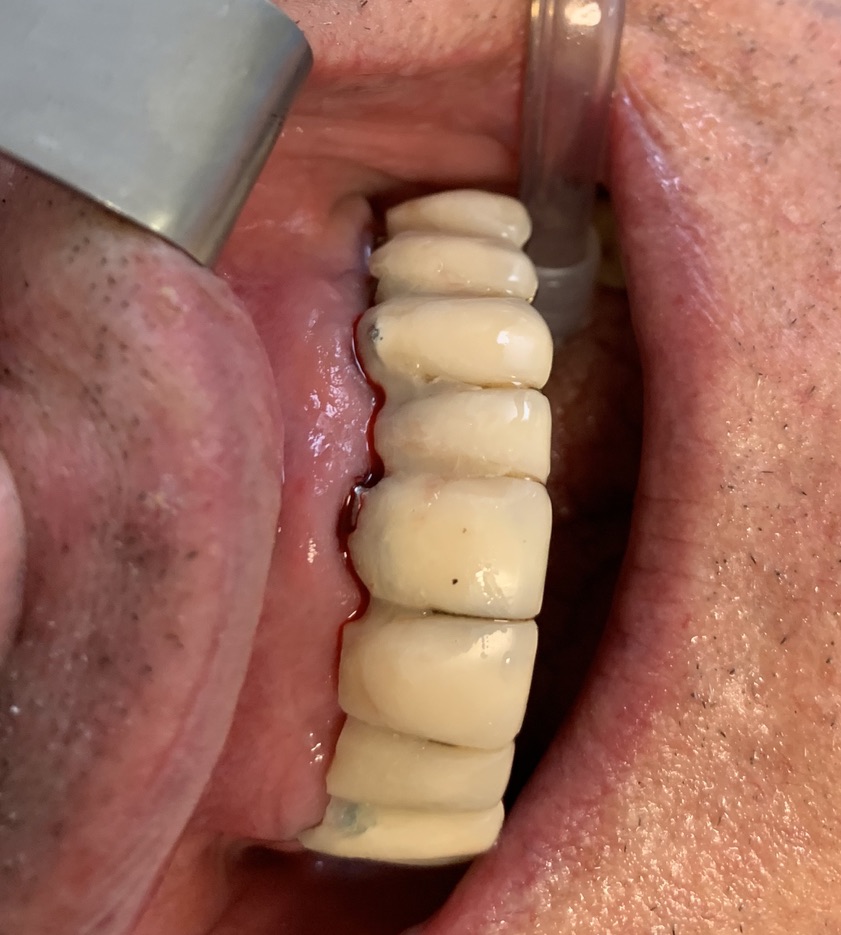

Implant type: Tramonte     No. Implants inserted: 2       Welding: No      Dental area: 21   23

Intraoral Rx app: Vix win       CT scan: No      Extraction situation: immediate post extraction implants        Density according to Misch: D2

Occlusal load: immediate     Complications: none      Video or written statement of satisfaction: video su Iophone xs.